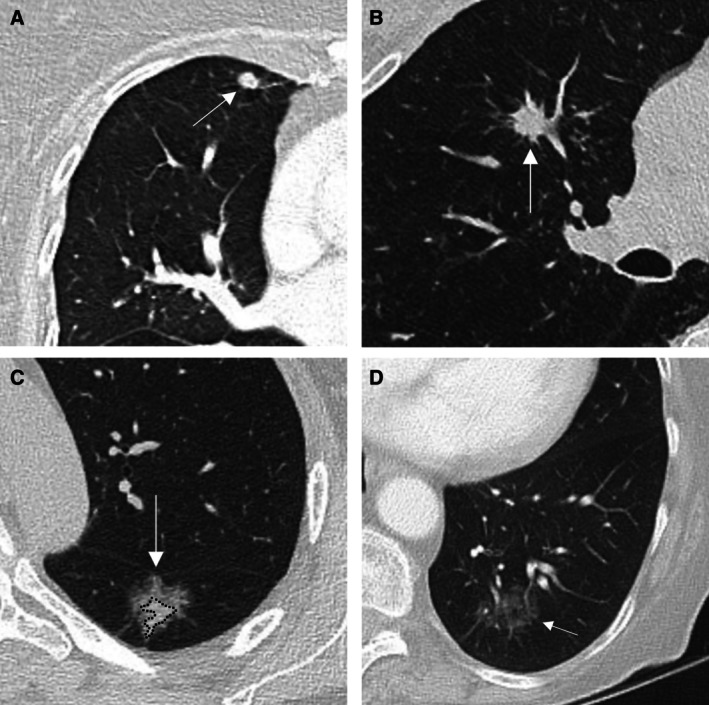

越来越多的肺癌筛查项目的采用和成像技术的进步显著增加了肺结节的检测,无论是偶然的还是通过筛查。本文件为临床医生提供了一个全面的指南,以解决管理不确定肺结节(ipn)的复杂性,强调以人为本和多学科的护理。ipn根据大小和形态进行分类,并有恶性肿瘤风险分层、诊断评估和随访的具体指南。专门的肺结节评估小组(LNETs)和结节多学科会议(MDMs)在确保指南遵守、简化诊断途径、减少不必要的调查和改善结果方面发挥着关键作用。结构化IPN项目在早期肺癌检测、改善早期肺癌检测和减少治疗启动延迟方面已经证明了益处。有效的管理策略包括使用标准化的报告模板,利用经过验证的风险模型,如PanCan恶性肿瘤风险模型和议定的ipn后续协议。本文档强调了获取先前成像以评估生长和计算计算机断层扫描(CT)扫描之间的技术差异的重要性。任何被认为正在生长的结节都需要在结节MDM上进行讨论,并决定酌情进行组织活检。基于结节特征和风险概况,结节MDM有助于优化最安全、最有效的活检技术。通过整合多学科专业知识和坚持以证据为基础的协议,服务可以改善ipn的及时诊断和管理,最大限度地减少过度调查,减少过度诊断的机会,并最终提高患者的预后和肺癌生存率。

The increasing adoption of lung cancer screening programs and advancements in imaging technologies has significantly increased the detection of pulmonary nodules, both incidentally and through screening. This document provides a comprehensive guide for clinicians to address the complexities of managing indeterminate pulmonary nodules (IPNs), emphasising person-centred and multidisciplinary care. IPNs are categorised based on size and morphology, with specific guidelines for malignancy risk stratification, diagnostic evaluation, and follow-up. Dedicated lung nodule evaluation teams (LNETs) and nodule multidisciplinary meetings (MDMs) play a critical role in ensuring guideline adherence, streamlining the diagnostic pathway, reducing unnecessary investigations, and improving outcomes. Structured IPN programs have demonstrated benefits in early lung cancer detection, improved detection of early-stage lung cancer, and reduced delays to treatment initiation. Effective management strategies include use of standardised reporting templates, utilising validated risk models such as the PanCan malignancy risk model and agreed protocols for follow up of IPNs. This document highlights the importance of accessing prior imaging to assess for growth and accounting for technical differences between computed tomography (CT) scans. Any nodule considered to be growing requires discussion at a nodule MDM with decision to act for tissue biopsy as appropriate. A nodule MDM will assist in optimising the safest and most efficient biopsy techniques based on nodule characteristics and risk profile. By integrating multidisciplinary expertise and adhering to evidence-based protocols, services can improve the timely diagnosis and management of IPNs, minimise over-investigation, reduce chance of overdiagnosis and ultimately enhance patient outcomes and lung cancer survival.